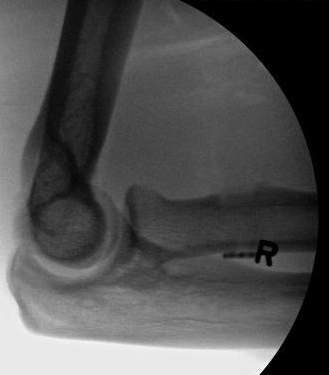

X-ray

Usually normal

Rarely see bony avulsion from radial tuberosity